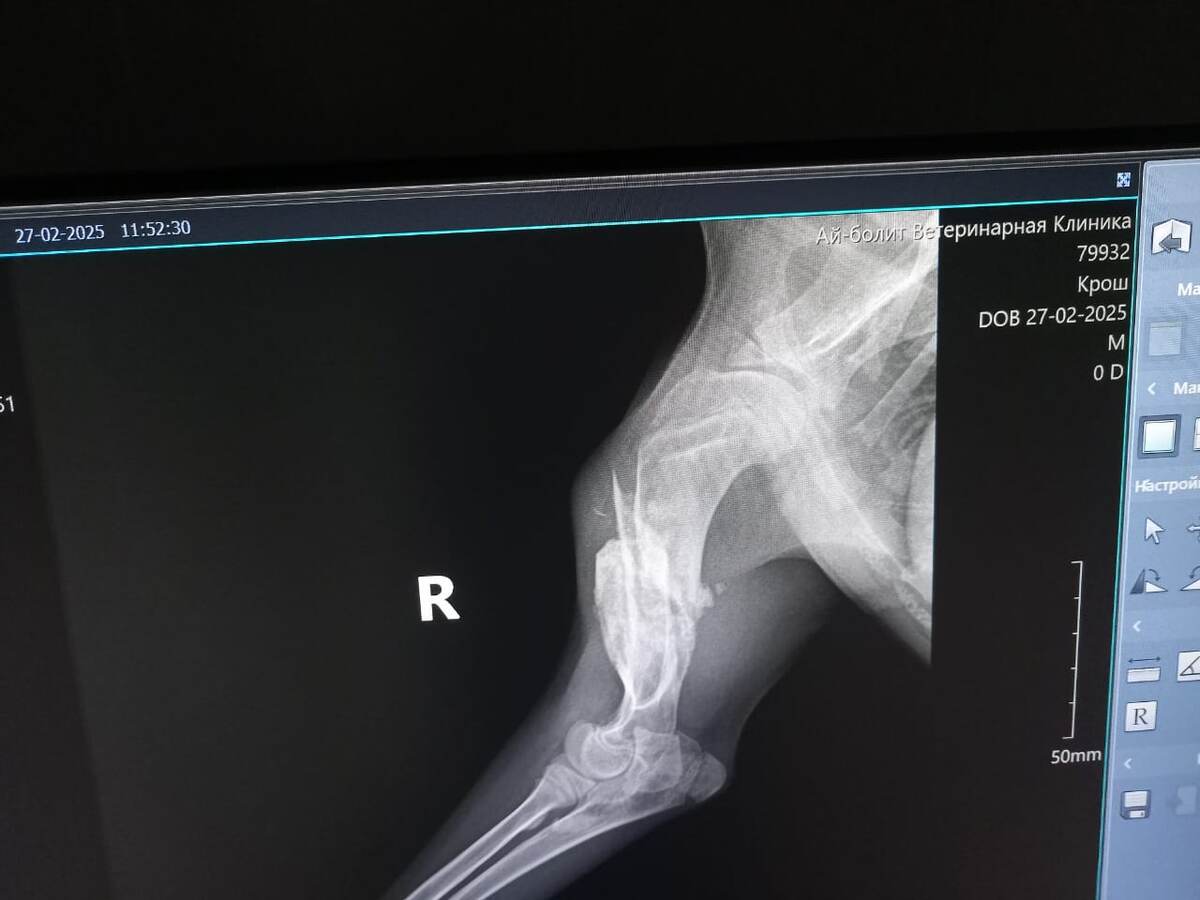

Свозили в клинику Кроша.

Сделали рентген, сдали анализы.

Всё же у него перелом. Старый, не правильно сросшийся. И лапа у него подгибается из-за повреждения сухожилий, нервных окончаний...

Дмитрий Викторович выйдет на работу на следующей неделе. Мы покажем мальчика еще ему. А пока рекомендованы массажи. Кроме того, у Кроша не очень хорошие анализы. Низковат гемоглобин. Рекомендованы витамины и усиленное питание. По мнению врача, сейчас делать операцию уже поздно и бессмысленно.